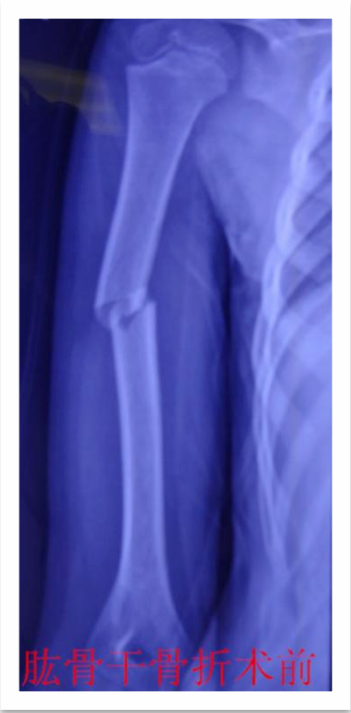

儿童骨折的微创治疗--四肢骨折的弹性髓内钉技术(骨科)

儿童四肢骨折较为常见,保守治疗仍是儿童骨折的重要 治疗方法之一,如牵引,单纯石膏固定等。 往往用时较长,患儿的舒适程度不够,影响患儿及时返回学校学习,这些因素越来越多地影响儿童骨折治疗方法 的选择 。儿童骨折手术治疗的比例较前增加,而传统的手术治疗创伤大,恢复慢,并发症多,如钢板,那是针对成人骨折研发的,用一个坚硬的内固定物固定一个有弹性的骨组织是一个矛盾 ,弹性髓内钉内固定解决了这个矛盾。有人说,弹性髓内钉的出现是上天对儿童的恩惠。的确,弹性髓内钉是治疗小儿长管状骨骨骨折的一种理想、可靠的内固定方法。弹性髓内钉技术发源于法国,在欧洲广泛应用后,现已为全球所接受,被称为是儿童骨科界的一次革命。徐州儿童医院骨一科应用弹性髓内钉技术治疗四肢长管状骨骨折,具有创伤小、恢复快、并发症相对少,孩子能较快恢复正常生活、学习等优点。该技术先将骨折闭合复位,通过微小的切口将特制的弹性髓内钉置入骨髓腔,达到固定骨折的目的。适用于肱骨,股骨,尺桡骨等部位的常见骨折(图)。